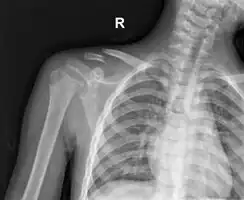

Clavicle fracture

The basic method to check for a clavicle fracture is by an X-ray of the clavicle to determine the fracture type and extent of injury. In former times, X-rays were taken of both clavicle bones for comparison purposes. Due to the curved shape in a tilted plane X-rays are typically oriented with ~15° upwards facing tilt from the front. In more severe cases, a computerized tomography (CT) or magnetic resonance imaging (MRI) scan is taken. However, the standard method of diagnosis through ultrasound imaging performed in the emergency room may be equally accurate in children.[6]